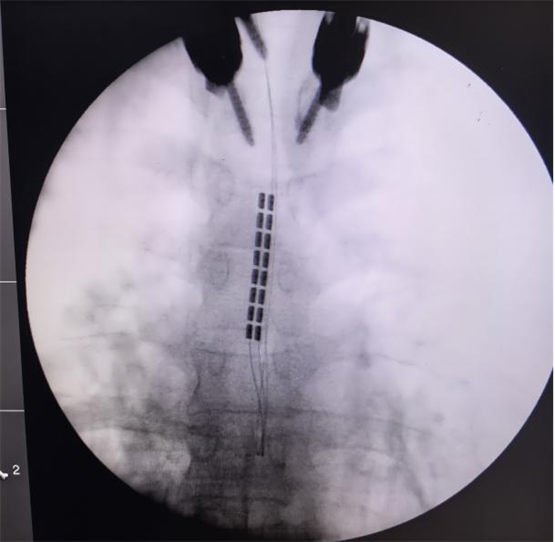

经过严格的术前讨论,团队决定为孙女士施行颈段脊髓电刺激(SCS)植入术。手术由陈菊祥教授主刀,在C臂X光机精准引导下,将刺激电极植入颈髓(C2-C4水平)硬膜外腔的中线位置。

为避免对患者脊髓功能造成任何医源性损伤,团队在术中全程采用了影像导航系统,以及多模式神经电生理监测,包括连续脑电图(EEG)、体感诱发电位(SSEP)等,实时监控神经系统功能状态,为手术安全上了“双保险”。“手术精度要求达到毫米级,确实是刀尖上起舞,“陈菊祥教授如此形容,”术后我立刻查看了影像,确认电极位置精准。”